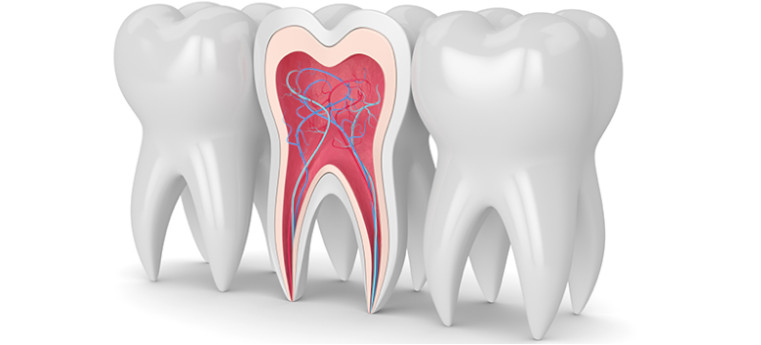

O tratamento de canal inicia geralmente pela remoção do tecido cariado que o dente possui. A realização do tratamento de canal é sempre que a polpa(parte de dentro de um dente) dentaria foi atingida por uma carie mais profunda,fazendo o contato ao nervo que nos dá o sinal de que algo anormal está ocorrendo, assim ocasionando a dor de dente.

O tratamento consiste na inserção de limas para realizar a instrumentação dos canais radiculares. Após o tratamento de canal o dente ficará sem a polpa e dependendo do grau de destruição causado pela cárie ou trauma que o dente tenha sofrido deverá ser feita uma reabilitação através de uma prótese fixa como um bloco ou uma coroa.

Remoção da polpa infeccionada: Os canais são esvaziados, descontaminados, alargados e alisados. Nessa parte, são utilizadas limas especiais e ferramentas para irrigação.

Obturação dos canais: para finalizar o tratamento, os canais são preenchidos permanentemente com um material específico, fazendo o selamento. O resultado final ainda pode ser protegido com uma coroa, prótese parcial que envolve todas as faces dentárias, que é cimentada no dente restaurado.